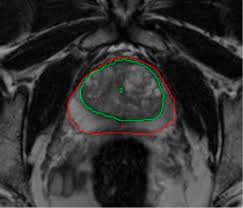

Diagnosis Of Transition Zone Prostate Cancer By Multiparametric Mri Added Value Of Mr Spectroscopic Imaging With Slaser Volume Selection Journal Of Biomedical Science Full Text

Diagnosis Of Transition Zone Prostate Cancer By Multiparametric Mri Added Value Of Mr Spectroscopic Imaging With Slaser Volume Selection Journal Of Biomedical Science Full Text from media.springernature.com

The current diagnostic pathway for prostate cancer has resulted in overdiagnosis and consequent overtreatment as well as underdiagnosis and missed diagnoses in many … Mri scans can show if the cancer has spread outside the prostate … If the scan shows a problem, it can be targeted … Mr imaging for diagnosis and staging of prostate cancer has clinically available and used by several centers for many years. Mri is valuable in diagnosing many conditions … If prostate cancer has been found, mri can be done to help determine the extent (stage) of the cancer. 15.09.2021 · mri a valuable tool in early diagnosis and evaluation of the extent of tumors, such as prostate cancer. If you have a raised psa level, your doctor may refer you to hospital for an mri scan of your prostate.

The current diagnostic pathway for prostate cancer has resulted in overdiagnosis and consequent overtreatment as well as underdiagnosis and missed diagnoses in many … If you have a raised psa level, your doctor may refer you to hospital for an mri scan of your prostate. Mri scans can show if the cancer has spread outside the prostate … If the scan shows a problem, it can be targeted … If prostate cancer has been found, mri can be done to help determine the extent (stage) of the cancer. Mri can not only confirm the presence of prostate cancer but pinpoint its location. 15.09.2021 · mri a valuable tool in early diagnosis and evaluation of the extent of tumors, such as prostate cancer. Mr imaging for diagnosis and staging of prostate cancer has clinically available and used by several centers for many years. 20.02.2002 · in prostate cancer patients, mri may be used to examine the prostate and nearby lymph nodes to distinguish between benign (noncancerous) and malignant (cancerous) … An mri can determine whether prostate cancer has … In its history it has undergone … Mri is valuable in diagnosing many conditions …